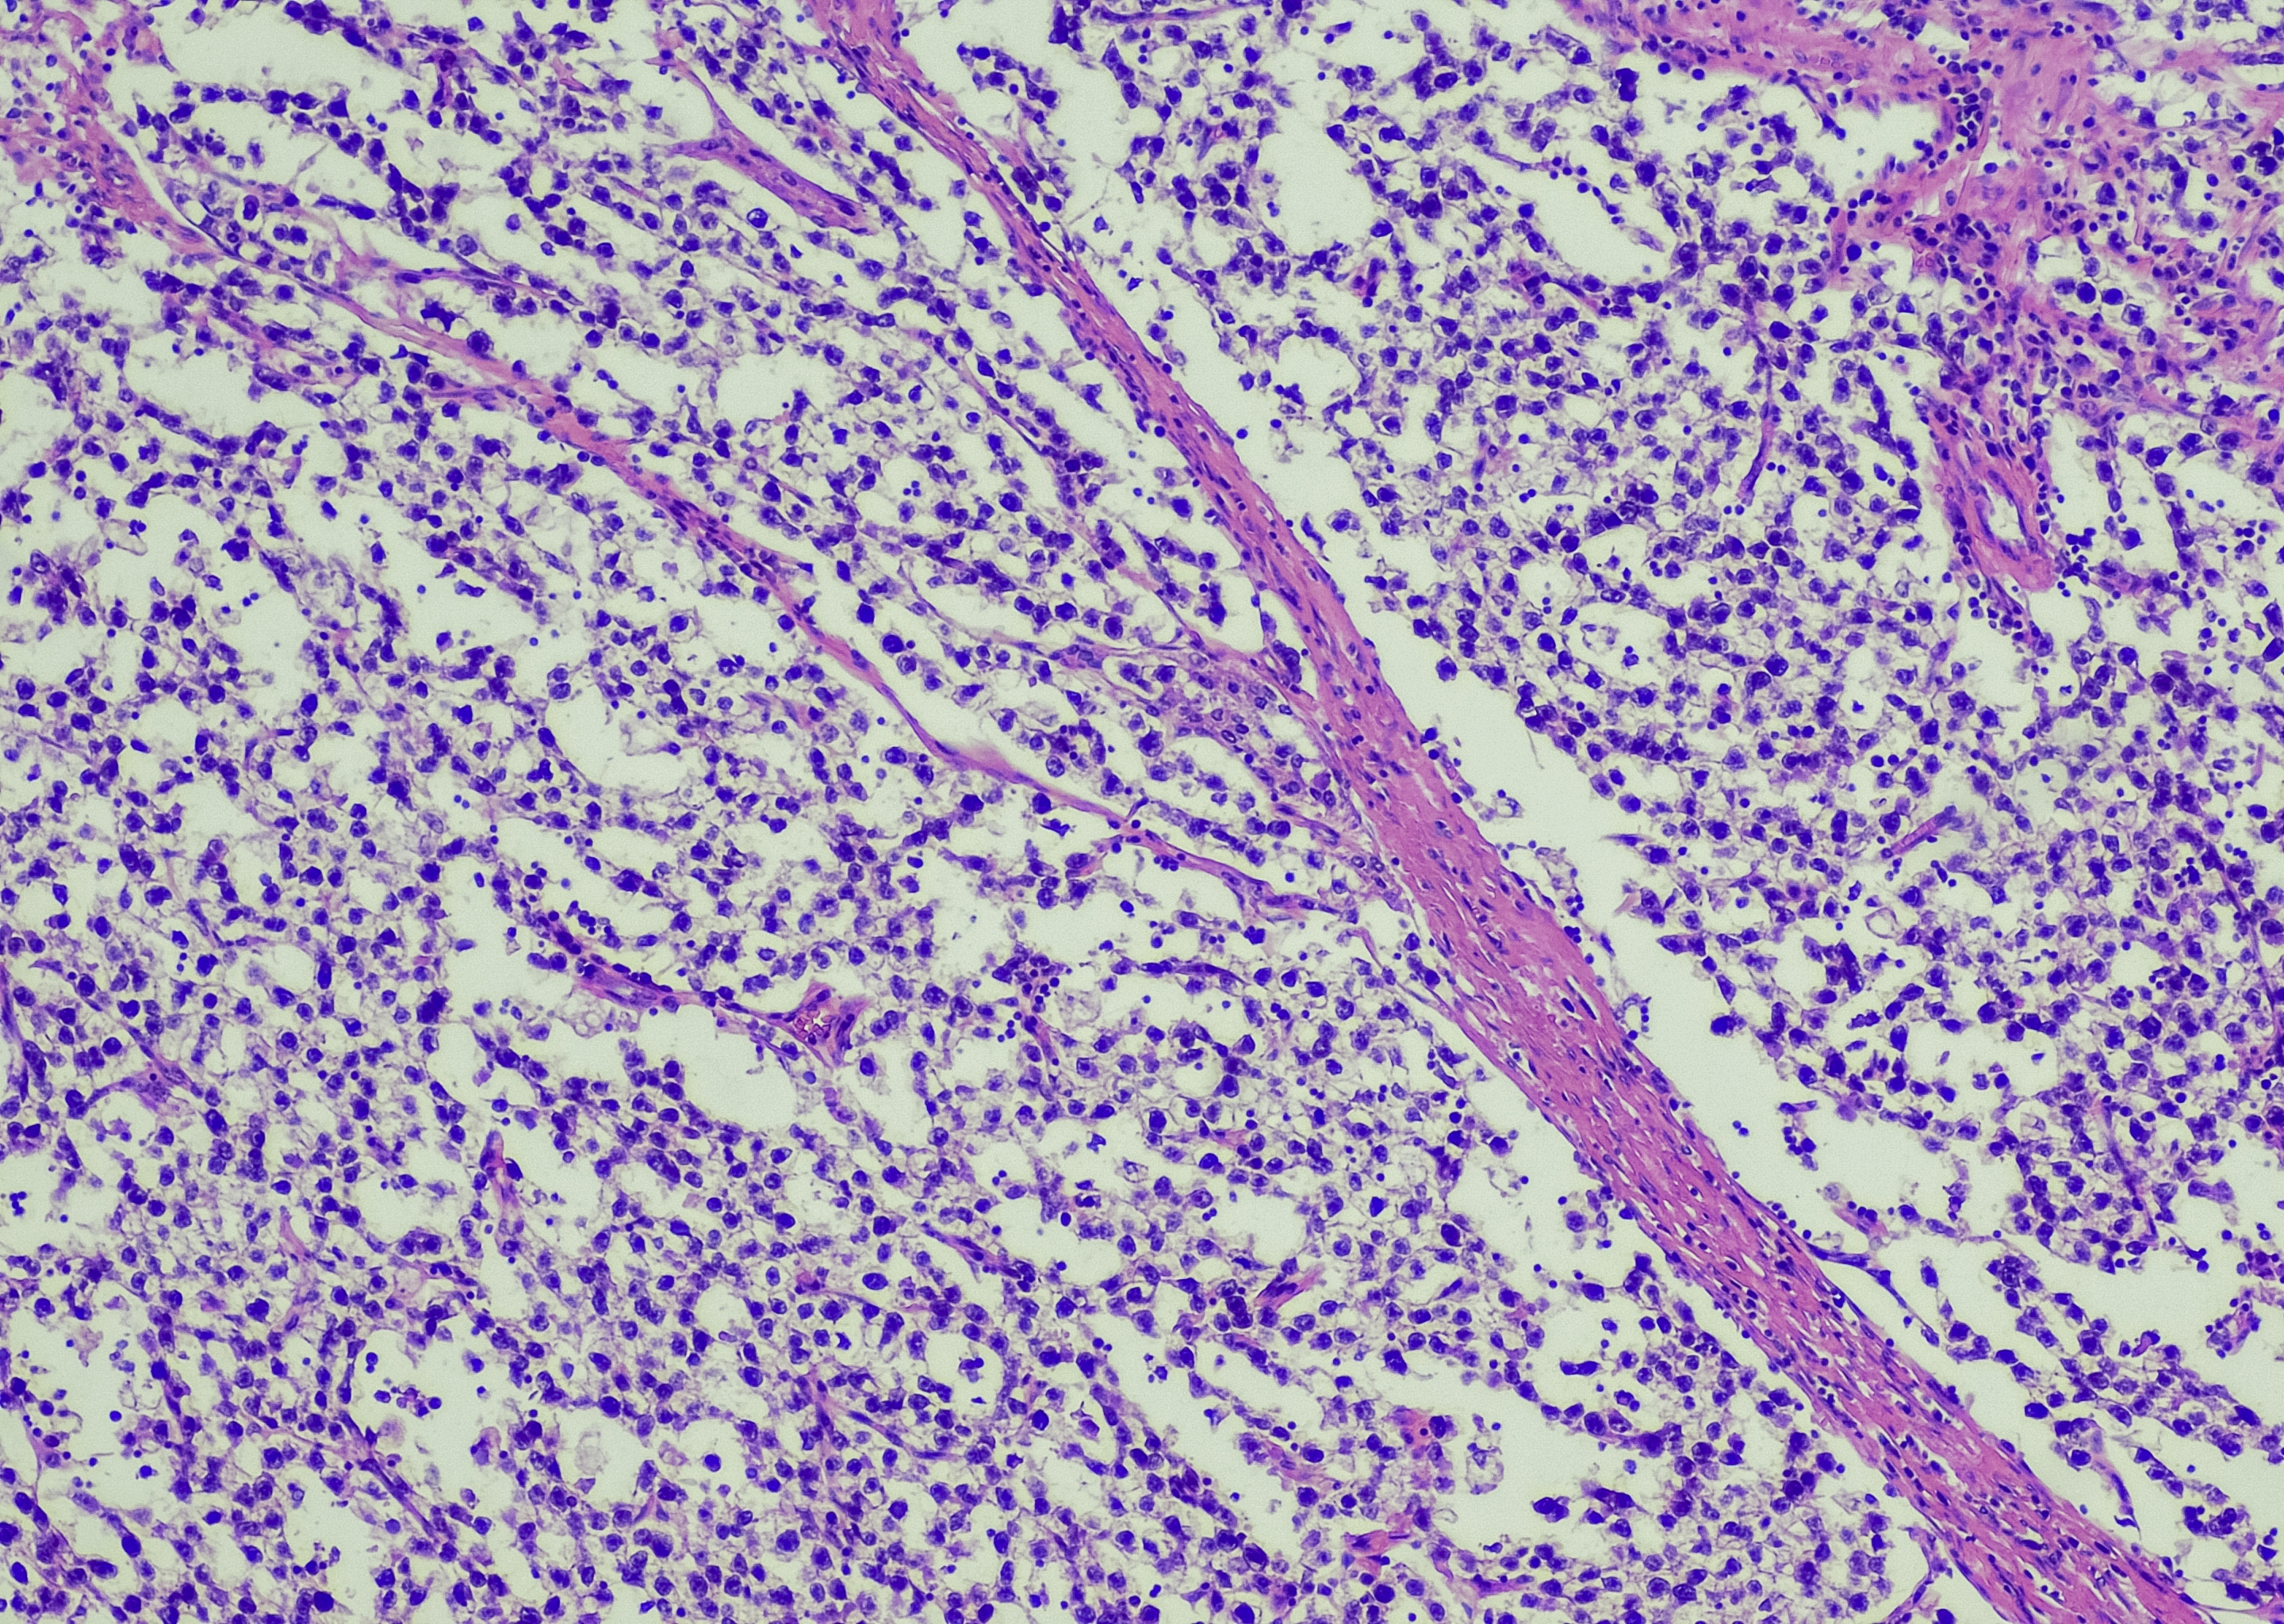

Seminomas

Seminomas grow and spread slower than non-seminomas. There are 2 subtypes:

- classical (typical) seminoma: most seminomas are classical seminomas

- spermatocytic seminoma: a rare type of seminoma that tends to affect older men. These are slow-growing and not likely to spread.